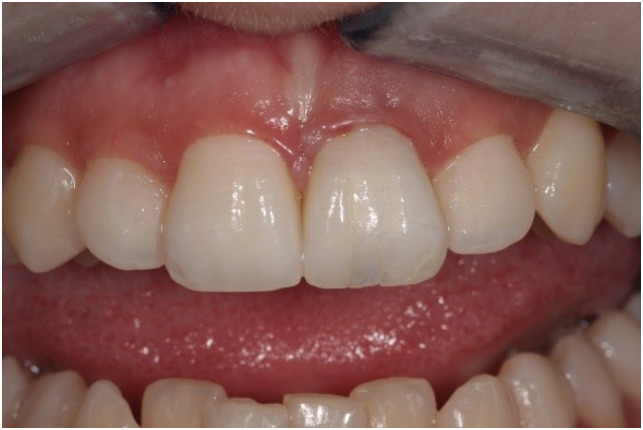

Figure 4

Final outcome after intracoronal bleaching and permanent composite restoration.

The working length was established with an electronic apex locator (Root ZX, J. Morita Corp., Tokyo, Japan) and confirmed via radiography. The canal was subjected to instrumentation only with NiTi files (K-File Nitiflex, Dentsply-Maillefer, Ballaigues, Switzerland), stainless steel hand files (K-File, Dentsply-Maillefer), and Hedstrom files (ReadySteel, Dentsply-Maillefer). The last instrument used for apical preparation was a size 120 file, and at that point a definite apical stop could be established. The site was irrigated with copious amounts of 5% sodium hypochlorite. At the time of drying, the electronic apex locator, the hand files, and the paper points indicated no sign of perforation. At the most apical part of the resorption defect, the root canal appeared extremely thin; thus, the use of warm gutta-percha for obturation was deemed risky and difficult to control. An approximately 4- to 5-mm-thick mineral trioxide aggregate (MTA) plug (MTA+, CERKAMED Medical Company, Stalowa Wola, Poland) was made to establish a proper apical barrier without error in the affected apical part (Figure 3). The MTA was covered with a moist cotton pellet, and the tooth was temporized with Cavit W filling material (3M ESPE, Seefeld, Germany) for 48 hours. At the next appointment, the root canal was adhesively treated with a dual-cure self-etch adhesive system (Gradia Core Self-Etching Bond, GC Europe, Leuven, Belgium) and was filled with SFRC (EverX Posterior, GC Europe) according to the Bioblock technique [15] to the point of the root canal orifice. During this procedure, an approximately 4-mm-thick increment of SFRC material was placed in the root canal and applied to the most apical part to make contact with the MTA plug. This can be accomplished by pressing alternately with any small-headed microbrush and a periodontal probe or plugger. After the first layer appeared to be in position, a light-transmitting FRC post (1.4 mm GC Fiber Post, GC Europe) was inserted into the canal to facilitate the transmission of the light to the apically-positioned layers. The light-transmitting post was withdrawn to 0.5–1 mm from the surface of the uncured SFRC layer so as not to directly contact it. The first layer of SFRC was light-cured through the post for 80 seconds using a light source with an average power density of 900 mW/cm2. This was continued to the level of the cemento-enamel junction. After the root canal was filled to that level, the coronal portion of the tooth was internally bleached several times with sodium perborate (made by the pharmacy of the University of Szeged) mixed with distilled water at a ratio of 2:1 (g/mL) and covered with glass ionomer filling (Equia Fore, GC Europe). After the desired color was reached, the coronal cavity and the SFRC material in the orifice were refreshed with a diamond bur, adhesively treated (G-premio Bond, GC Europe), and restored with SFRC and a 2-mm-thick composite covering on the palatal aspect (G-aenial Anterior, GC Europe) (Figure 4).